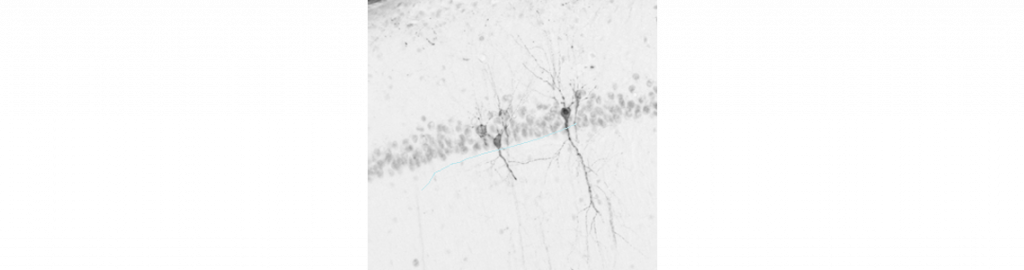

Pour élucider la toxicité des DNF in vivo, nous avons généré un modèle de tauopathie, appelé modèle « pro-agrégation » chez le rat qui génère un grand nombre de DNF dans l’hippocampe. Ce modèle est basé sur l’expression simultanée de la protéine Tau humaine sauvage et d’un peptide pro-agrégation via l’utilisation de vecteurs adéno-associés (AAV). Il est caractérisé par une forte hyperphosphorylation pathologique de la protéine Tau, la localisation aberrante de la protéine dans le soma et les dendrites neuronaux et la présence de nombreuses DNF argyrophylles dès un mois après l’injection du vecteur AAV, similaires aux lésions retrouvées chez les patients. En comptant le nombre de neurones CA1 de l’hippocampe, nous avons montré que la présence de DNF ne provoque pas de mort neuronale au moins jusqu’à 3 mois après injection. A l’inverse, la surexpression de la protéine Tau humaine sauvage seule provoque une mort neuronale importante de ces mêmes neurones, ainsi qu’une forte hyperphosphorylation de Tau mais cette fois, en l’absence totale de DNF.